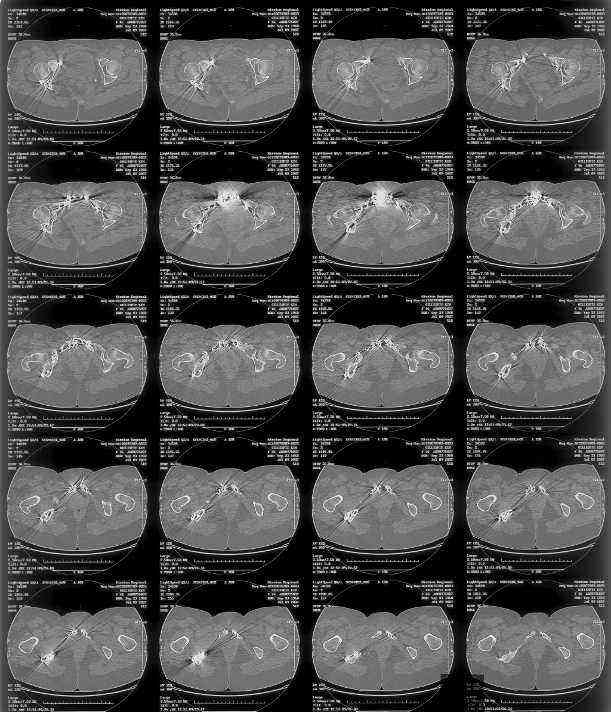

I can't see the axial CT images well enough to detail the potential sacral issues....can you magnify them?

Here is a magnified view. Sorry about the quality but the CT was scanned into our system.